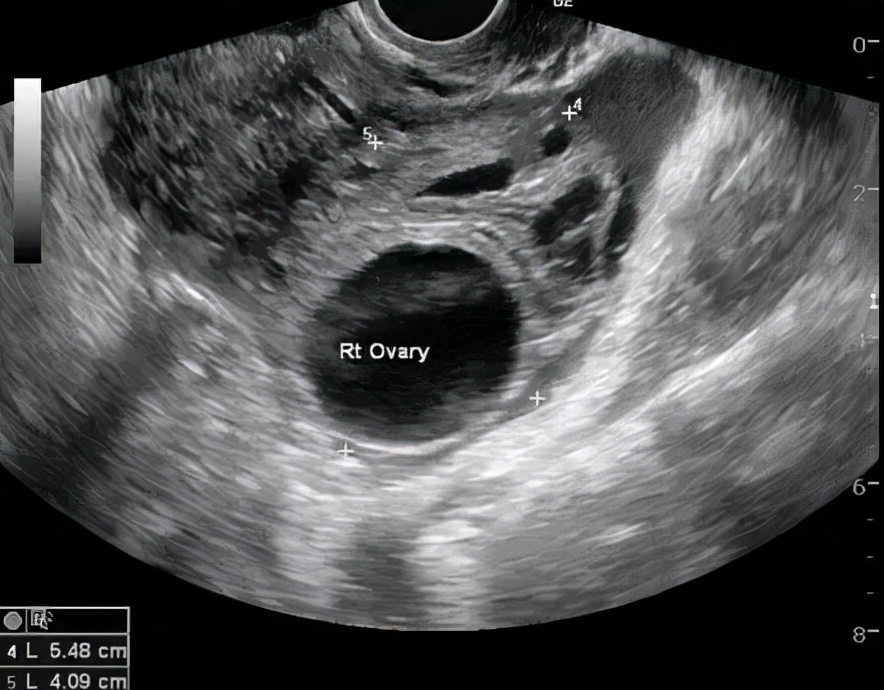

卵巢生理性囊肿特点: 囊壁菲薄,内壁光滑,透声好,直径基本<4-5cm。超声多普勒血流检测提示没有明显的血流信号。多数会消失,一般建议1-3个月后月经干净3天左右复查,因为这时新的一批卵泡尚未发育起来,所有没有二次干扰,可以判断它是否真的消失了。